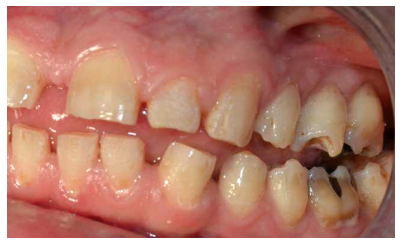

- A nivel dentario, el esmalte es uniformemente anormal, delgado, rugoso e hipoplásico. Afecta a ambas denticiones, y provocando una marcada frecuencia de fracturas dentarias, desgastes o abrasiones y caries. Existe un importante componente lingual en maloclusión, diastemas en toda la arcada y prognatismo mandibular, así como bruxismo y patología de ATM. Incisivos con forma de pala y molares cóncavos que favorece las lesiones de caries y sensibilidad dentinaria.

En la mayoría de los niños se pueden observar características dentales como cúspides puntiagudas, incisivos en forma de pala, esmalte delgado y superficies bucales con hoyos. Además, la ATM puede verse afectada con una reabsorción severa de la cabeza del cóndilo36 (Figuras 9-11).

El examen histológico de los molares primarios exfoliados mostrará una banda de porosidad aumentada a continuación de las estrías de Retzius en la parte exterior del esmalte. Estas alteraciones del desarrollo se asocian ocasionalmente con defectos menores localizados en la superficie del esmalte37.

Conviene enfatizar además la importancia de una vigilancia cercana al desarrollo dental y al cuidado bucal de manera regular para prevenir el desgaste de los dientes, la pérdida de la altura vertical de la superficie oclusal y el riesgo subsecuente de disfunción de la articulación temporomandibular (ATM).

Los pacientes con síndrome de Morquio, a menudo, necesitan tratamiento de ortodoncia para la corrección de la maloclusión, lo que a su vez mejora la función masticatoria. Se podrían corregir las inclinaciones labiales de los dientes anteriores superiores e inferiores y se cerrarían los espacios interdentales para una correcta higiene, evitándose así la aparición de caries37.

Estos pacientes muestran arcos maxilares y mandibulares espaciados con un hábito de empuje lingual a la vez que también suelen presentar un labio superior sobresaliente, inclinación labial de los dientes anteriores superiores e inferiores y esmalte delgado. El hábito de empuje de la lengua suele desaparecer después de la aplicación de un aparato de ortodoncia removible. La dentición espaciada en los arcos superior e inferior mejora después del tratamiento con un dispositivo fijo con cable de arco de bucle de cierre (0.017 x 0.025) y bandas en los molares superiores e inferiores, sin utilizar dispositivos de borde debido a la fragilidad y mala calidad del esmalte38.